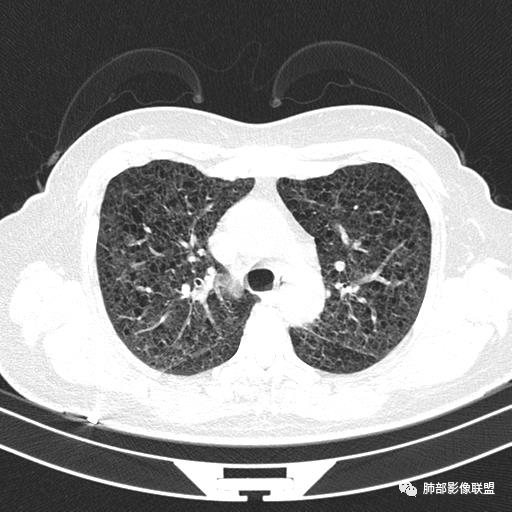

中年女性,不吸烟

双肺弥漫囊腔,累及肋膈角,囊腔形态相对规则单一。

符合LAM

CT平扫示双肺弥漫分布大小不等囊状薄壁透光区,无内、中、外带分布差异,间质稍示增厚。拟LAM

中年女性育龄期妇女,咳嗽气喘,无吸烟史,有苯吸入史。影像:双肺弥漫均匀小囊腔,无明显分布优势,囊腔形态欠规则,壁薄,部分囊腔边缘血管征,伴双肺弥漫磨玻璃影,无结节,考虑lam,鉴别苯中毒肺损伤,囊腔多有分布优势,小叶中心分布为主,形态规整等

女,46,活动性气喘1年。苯吸入史半年。胸部CT:两肺弥漫囊腔,上至肺尖,下至肋膈角,形态类似小囊腔。考虑:LAM,鉴别LIP,BHD,PLCH等。

双肺弥漫大小不一薄壁含气囊腔,囊间肺组织正常,正常肺背景,肺尖肺底受累;青年女性,气喘,支持LAM

双肺多发大小相近的囊状影,分布趋势趋于一致,中年女性,考虑LAM。部分囊内见血管及分隔影,小叶中心性肺气肿代排

CT表现:双肺弥漫大小不等的薄壁囊腔,囊壁<2mm,外形规则,血管影多位于囊腔周围,囊腔之间肺组织正常,随着疾病进展到晚期,囊腔变大、增多,不可胜数,囊腔可融合成较大的囊,与肺气肿相似,形成间质性肺纤维化。部分病例可出现结节影。